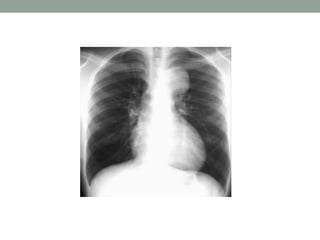

On the PA film there is a

lobulated paratracheal

stripe on the right.

On the lateral radiograph

there is a density overlying

the ascending aorta and

filling the retrosternal

space.

These findings indicate a

mass in the anterior as

well as in the middle

mediastinum.

The CT confirms the presence of lymphomas in both the

anterior and the middle mediastinum.